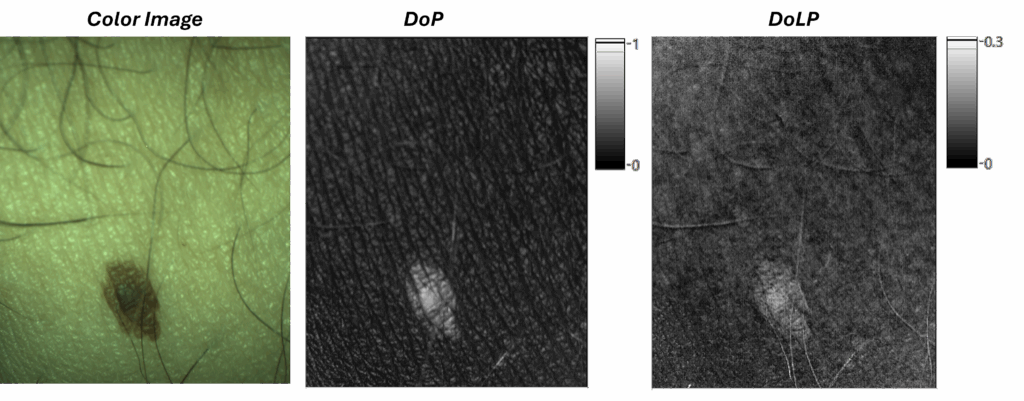

Quantitative Analysis of Skin Lesions

The Polvision Dermatoscope provides enhanced data to facilitate the differentiation of benign and malignant skin lesions. By analyzing a lesion’s complete polarization signature—the system can detect subtle changes in tissue architecture that are invisible to the naked eye.

Generally, high melanin content in a lesion (which will make it appears dark) increases the DoP. This occurs because melanin’s strong light absorption dramatically reduces multiple scattering which is the primary depolarizing effect. However, this DoP elevation will occur in both benign and malignant lesions, so additional contrast is needed.

- Benign Lesions (e.g., Nevi): These features are typically non-invasive. Even if highly pigmented (which will highly increases the DoP), they preserve the organized, birefringent collagen network of the dermis. This results in a significant high Degree of Linear Polarization (DoLP), indicating structural integrity. I.e. the collagen matrix will convert part of the incomming circular polarizated into linear polarization.

- Malignant Lesions (e.g., Melanoma): Malignancy is characterized by invasive, chaotic growth that actively degrades and destroys the dermal collagen network. This architectural breakdown causes a significant loss of birefringence and a corresponding low levels of DoLP signal (note that DoCP and DoP will be still high for heavily pigmented lesions).